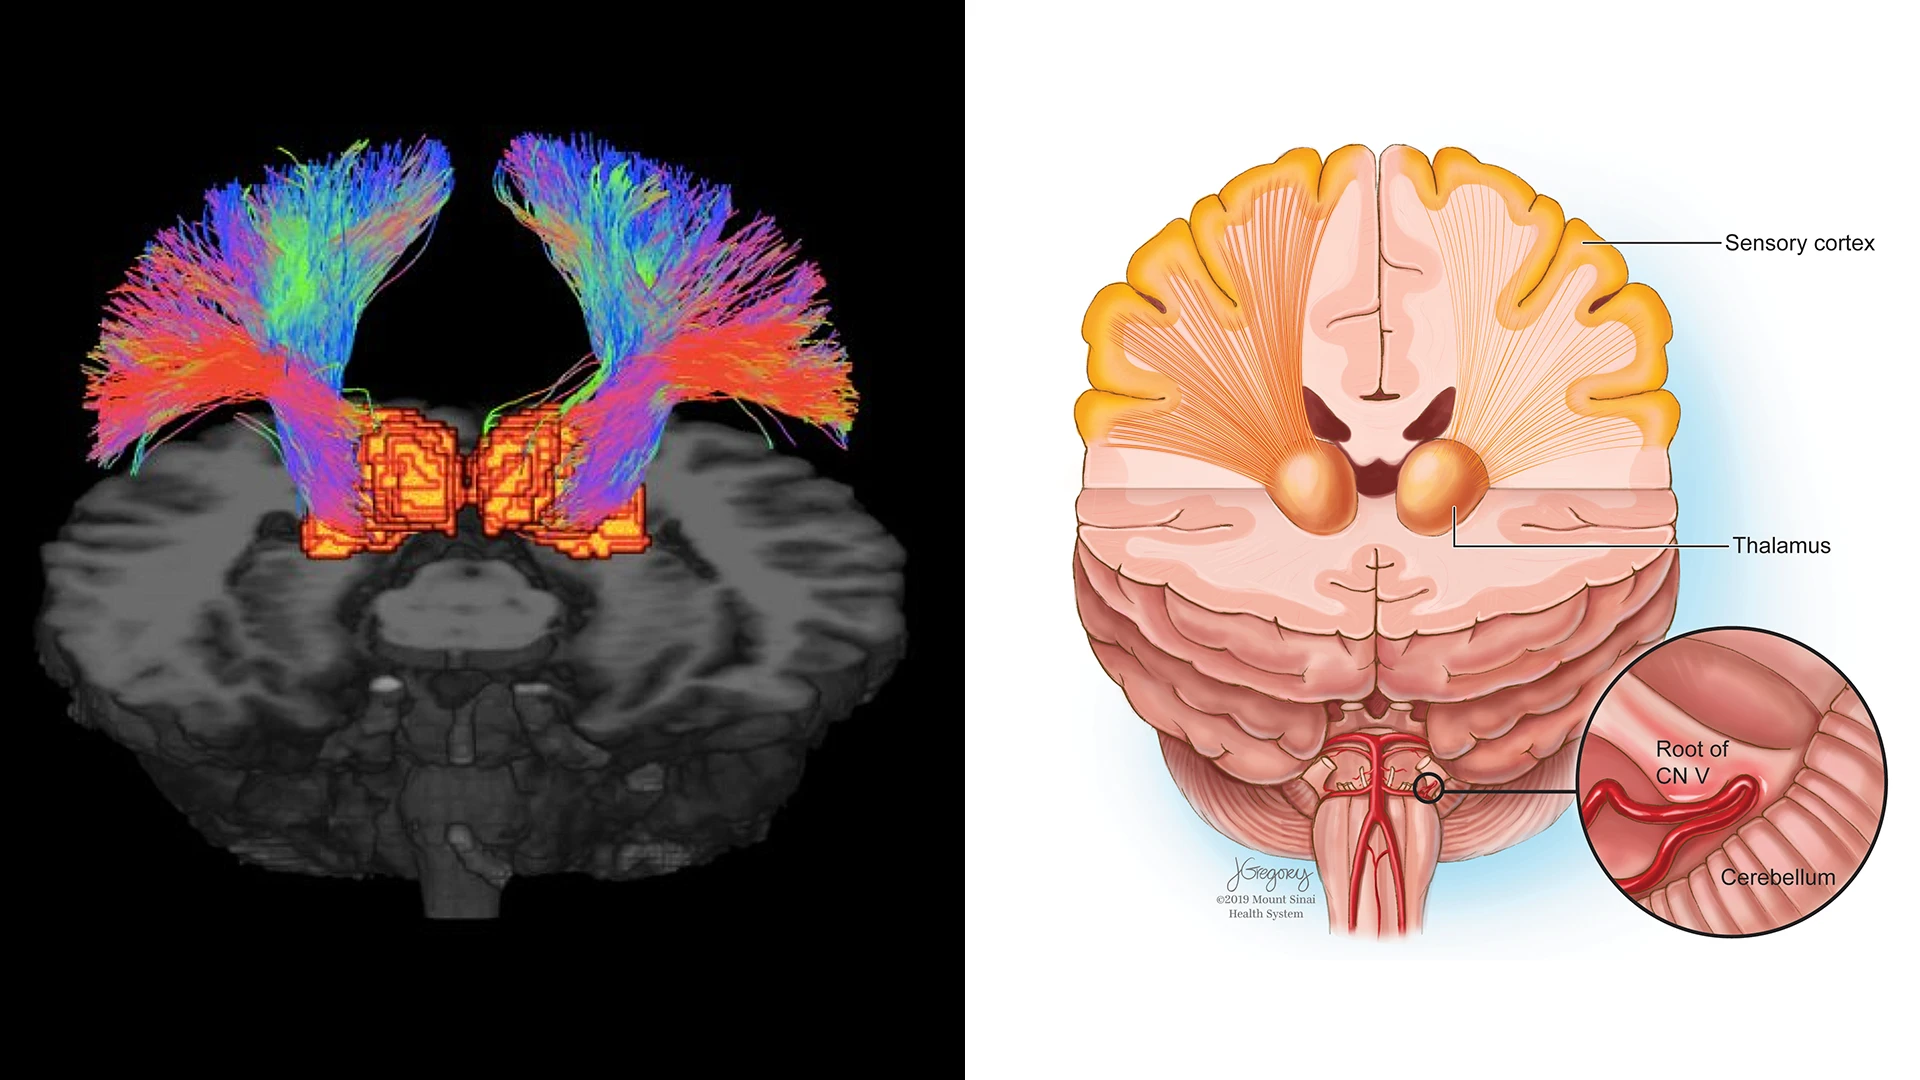

Figure 3. Probabilistic tractography of the thalamic-somatosensory tracts. Trigeminal neuralgia (TN) patients exhibited reduced integrity of these tracts on the ipsilateral side when compared to controls. These depict the white matter tracts connecting the thalamus to the somatosensory cortex in TN, a debilitating neuropathic pain condition that is often misdiagnosed due to lack of etiological understanding. 7-T diffusion weighted MRI (dMRI) is ideal for detecting changes in microstructure and integrity of white matter tracts and nerve fibers.